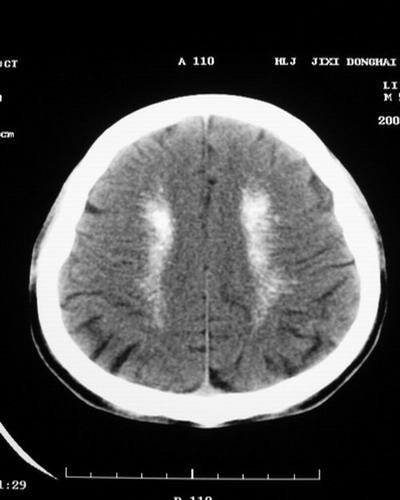

以下是引用随光逐影在2008-1-14 17:26:00的发言:[br]考虑为:甲状旁腺功能低下。需与fahr`s病相鉴别。建议:实验室检查。